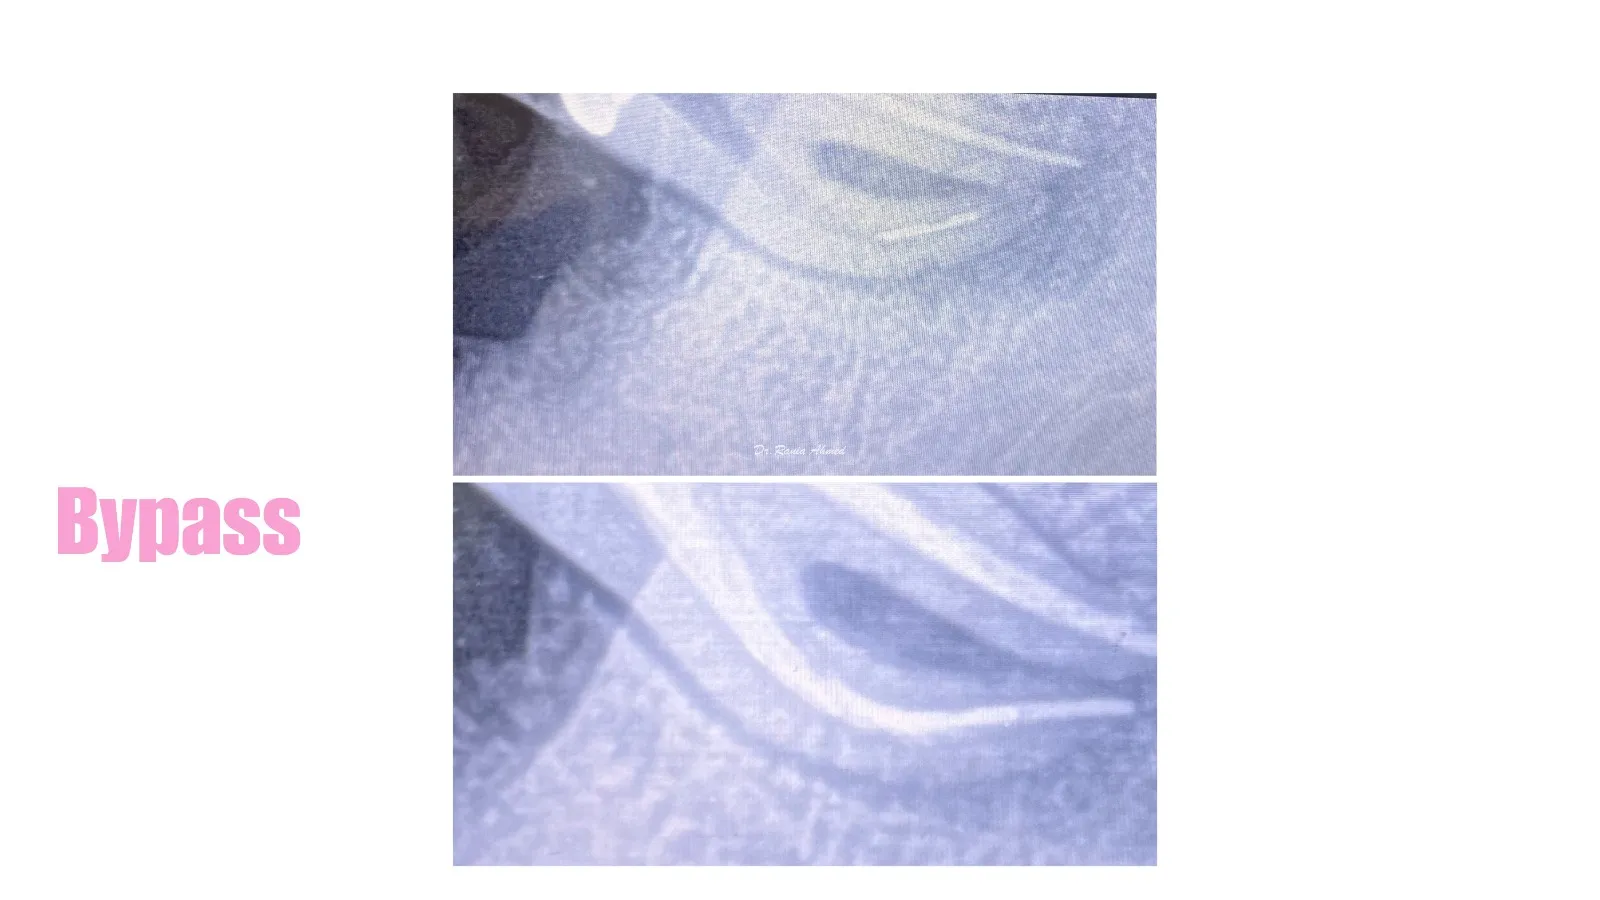

Endodontic Treatment